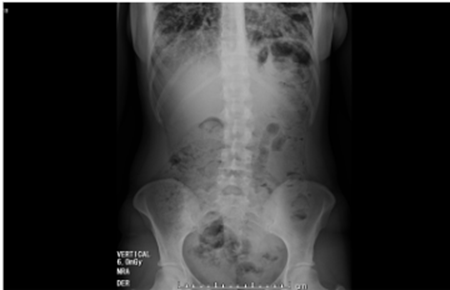

Continuó hospitalizada para completar estudios y al decimoprimer día de hospitalización presenta dolor abdominal epigástrico asociado a náuseas, dos episodios eméticos y ausencia de deposiciones, por lo que es valorada por cirugía general quienes solicitan radiografía de abdomen en bipedestación (figura 2), en la que se observa abundante materia fecal en todo el marco cólico por probable estreñimiento, sin signos de obstrucción intestinal, neumoperitoneo, ascitis, ni calcificaciones patológicas, y ecografía de abdomen que reporta leve engrosamiento de las paredes del colon sigmoide, probablemente de origen inflamatorio, e interposición de gas en marco cólico derecho.